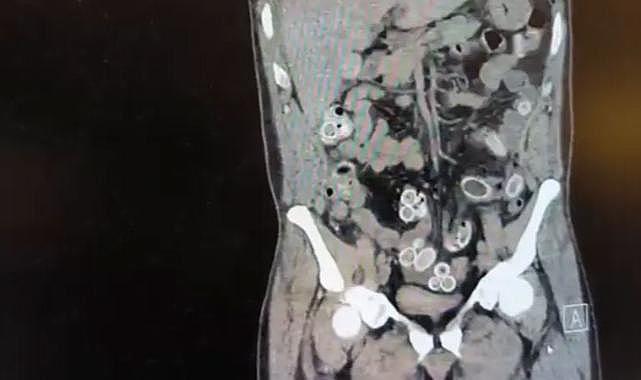

Beşiktaş’ta karın ağrısı şikayeti yaşayan Cüneyt G., Fulya’daki özel bir hastaneye başvurdu.Yapılan muayenenin ardından Cüneyt G.’nin tomografisi çekildi. Şüphelinin mide ve bağırsaklarında yabancı madde tespit edilmesi üzerine hastane yetkilileri durumu polis ekiplerine bildirdi.

İhbar üzerine çalışma başlatan Beşiktaş Asayiş Büro Amirliği ekipleri, doktorlarla görüşme gerçekleştirdi.Doktorların değerlendirmesi sonrası ameliyata alınan Cüneyt Ç.’nin bağırsaklarından, toplam ağırlığı 259,7 gram olduğu öğrenilen 49 esrar macunu çıkarıldı.Şüpheliye ait bir adet cep telefonu da hastane yetkilileri tarafından polis ekiplerine teslim edildi.